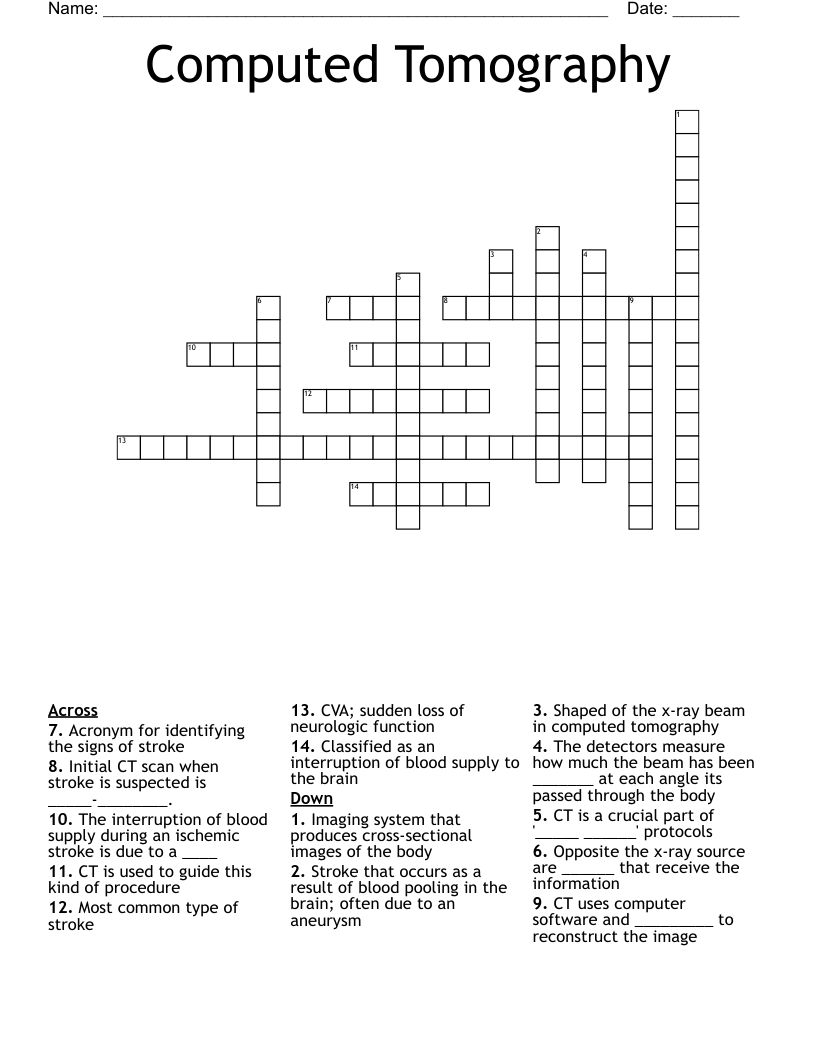

Computed Tomography Crossword WordMint